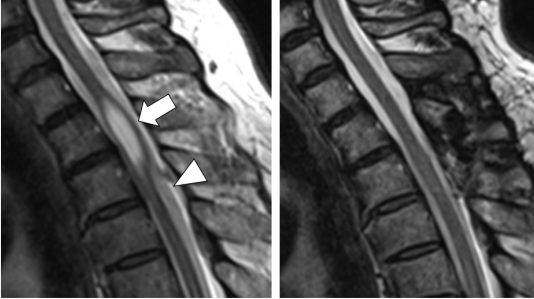

上位胸椎での脊髄空洞症:60歳代男性、両上肢しびれ感。両上肢と腋(わき)の下のしびれ感で受診。宙づり型の解離型温痛覚障害。初診時MRI(左)では上位胸椎レベルの脊髄内に空洞症を認めた(矢印)。空洞症を起こした脊髄の近くではくも膜のう胞(三角矢頭)が認められ、これが空洞症の原因と考えられた。手術でくも膜のう胞を除去し、脊髄および空洞症には処置を行わなかった。手術後3か月MRI(右)では空洞症が自然に消失した。感覚障害も改善した。(脊髄脊椎ジャーナル28(8)より)